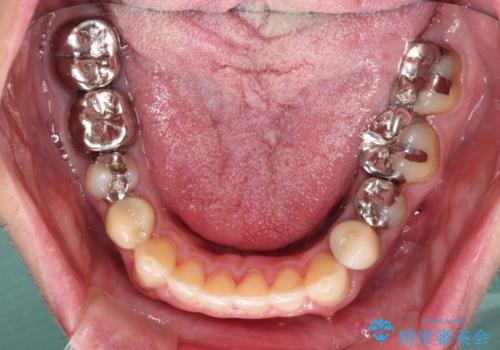

- 飛び出している上顎前歯と、奥歯に多くある銀歯を気にして来院された患者様です。

マウスピースで矯正を行いたい反面、一旦早めに前歯を整えたいというご希望があったため、まずは上顎前歯をワイヤー装置で整え、その後インビザラインにて仕上げていくこととしました。

矯正治療後には、奥歯の銀歯をすべてセラミックにて補綴治療することとしました。

ワイヤー矯正を併用したことで、上顎前歯はあっという間に整いました。

補綴治療にあたり、痛みのある歯に対して根管治療を行うこととしましたが、処置が必要な歯が多かったため、期間を要しました。

補綴治療中に前歯のデコボコが戻ってしまったため、補綴治療後にインビザラインを1セット追加して仕上げました。